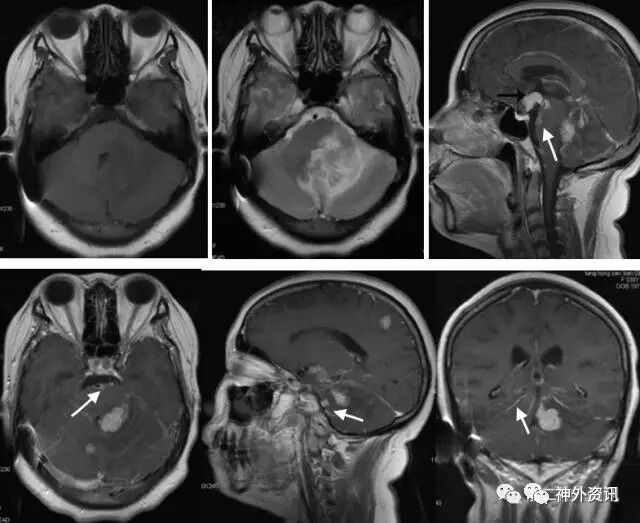

术后5月,患者诉头痛、呕吐来门诊复诊,复查头颅MRI平扫加增强显示:左顶叶,右小脑半球,第三、四脑室,鞍上池见斑片状长T1、长T2信号影,增强后明显强化;左侧小脑半球及桥脑脚大片T1低信号,T2高信号影,强化后桥臂病灶明显强化,同时可见桥脑腹侧面片状软脑膜增强影。诊断:脑内多发强化灶伴局部软脑膜强化,考虑转移瘤可能(图7)。

图7. MRI检查:左顶叶,右小脑半球,第三、四脑室,鞍上池见斑片状长T1、长T2信号影,增强后明显强化。

但患者V-P分流术后5月,因再次症状加重复诊,经检查提示颅内多发病灶以及脑膜强化。立体定向活检后证实为多发转移性肿瘤。回顾复习以前的MRI检查,发现早期在垂体柄漏斗部软膜已有转移,之后逐渐明显(图9)。说明该病例首次表现出来的颅高压是转移性肿瘤软脑膜转移为主的“脑膜癌病”所致。之后病情进展,演变为软脑膜转移和脑实质内多发转移共存的混合转移灶。

图9. MRI检查演变过程,A:首次MRI强化检查,见垂体柄漏斗部小片状强化,B:第二次检查片状强化较第一次明显,C:上述部位及整个脑干腹侧面大片软脑膜强化